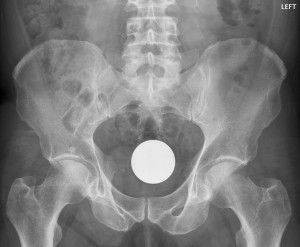

2. Bilardo topu